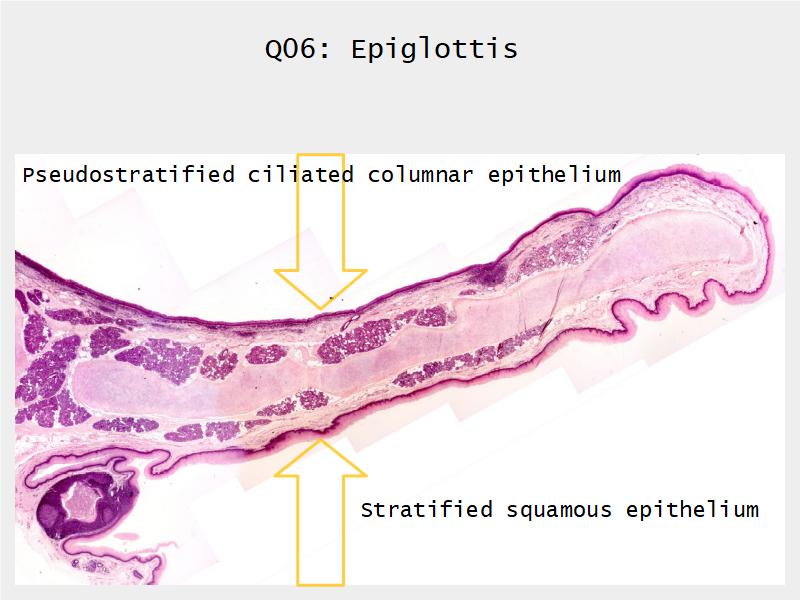

Respiratory epithelium

- Pseudostratified

- Ciliated

- Columnar

- Epithelium with

- 4 Cells

- Ciliated columnar cells

- Non-ciliated columnar cells

- Goblet cells

- Basal cells